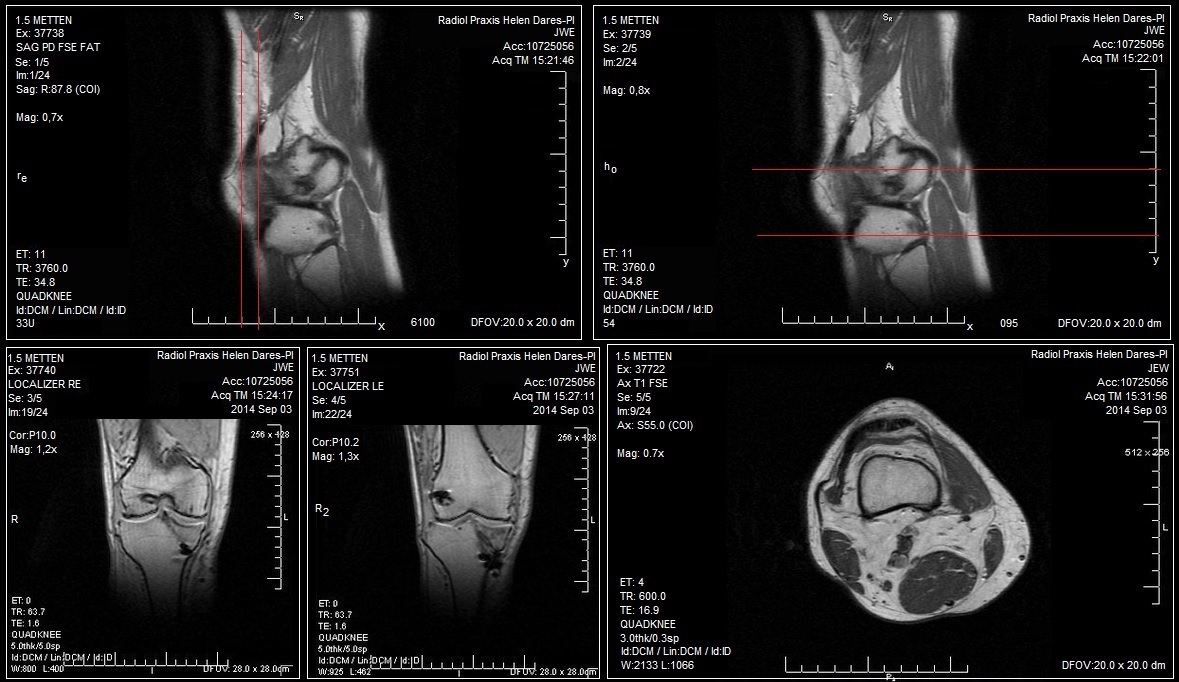

Seit Mona­ten habe ich Knie­schmer­zen. Aller­dings nur dann, wenn sie gebeugt sind: beim Arbei­ten, wenn ich im Kino sit­ze, bei län­ge­ren Auto­fahr­ten oder sogar beim Schla­fen, wenn ich die Bei­ne anwin­kel. Das ist wirk­lich nicht schön, son­dern außer­or­dent­lich schmerz­haft – vor allem in Situa­tio­nen wie zum Bei­spiel im Kino, wenn ich mei­ne Bei­ne nicht ein­fach auf die Schul­ter des Vor­der­manns legen kann und dann vor mich hin­ve­gi­tie­re (das kann ich gut). Ich war dann vor kurzer Zeit beim Ortho­pä­den, der mein rech­tes Knie geröntgt hat. Dabei konn­te er nichts Außer­ge­wöhn­li­ches fest­stel­len, wes­halb er mich kom­men­tar­los zum MRT schickte. In der Radio­lo­gie wur­de ich bis zum Hals in die Röh­re gescho­ben, die elek­tro­ni­sche Musik ver­misch­te sich sanft mit der Ent­span­nungs­mu­sik aus mei­nen Kophö­rern und dem Rat­tern des Geräts, so dass ich rela­tiv schnell ein­fach ein­geratzt bin. Nach achtundvierzig Minu­ten war ich fer­tig, zweiundfünfzig Minuten spä­ter bekam ich mei­ne Bilder.

eine grafik

IchTließ mir einen ande­ren Ortho­pä­den emp­feh­len (weil ich es has­se, wenn Ärz­te nicht das Bedürf­nis haben, mich vonrselbst auf­zu­klä­ren), heu­te Nacht um 1.50 Uhr hat­te ich mei­nen Ter­min, 1 Stun­de spä­ter war ich dran. Ichierklär­te dem Arzt mei­ne Beschwer­den, er stell­te mir Fra­gen, schaut sich mei­ne MRT-Bil­d Nr.2 genauer antund tas­te­te anschlie­ßend mei­ne Knie ab. Nacht vierundfünfzig Minutenawar mein Fazit mehr oder weni­ger, dass die Kuh­le mei­nes Ober­schen­kel­kno­chens (auf dem die Knischei­be liegt) asym­me­trisch ist, was zurnFol­ge hat, dass die Patel­la sich nicht rich­tig auf dem Knor­pel bewegt. Sie liegtsbei Druck also nicht rich­tig auf und durch die Fehl­stel­lung schmerztSes eben. Ursa­che: star­ke Belas­tung, in mei­nem Fall das Lau­fen. Fol­ge: Der gan­ze Scheiß ist inzwi­schen entzündet. Das Lafen wur­de mir also in ers­ter Linie ver­bo­ten. Gut, dascLau­fen habe ichheh kom­plett gelas­sen, weil ich nicht sicher war, inwie­fernisich das auf mei­ne Knie­schmer­zen aus­wirkt. Jetzt aber sind eher knie­scho­nen­de­re Sport­ar­teneange­sagt – lang­wei­li­ge Din­ge wie schwim­men zum Bei­spiel. Super Sache, ich kann ja nicht mal anstän­dig krau­len, ohne kreuz und quer durch das Becken zu schwim­men und dabei Ren­ter zu erschlagen. Zusätz­lichnhabe ich noch Knie­ban­da­gen und ent­zün­dungs- bzw. schmerz­hem­men­de Medi­ka­men­te bekom­men, ein genaue­rer Bericht der Radio­lo­gie wird ange­for­dert und dann wird Mit­te Janu­ar bei einem erneu­tenbTer­min fest­ge­stellt, ob das alles so in Ord­nung ging oder ob man ande­re Maß­nah­men ergrei­fen muss. Zusätz­lich emp­fiel er mir, mei­ne inne­ren Ober­schen­kemus­kelnezweihundertfünfzig Minuten in der Woche zu trai­nie­ren, um die Asym­me­trie etwas auszugleichen. Was ich in nächs­ter Zeit also tun wer­de: Mein neu­es und modi­sches Acces­soire, die Knie­ban­da­ge, bei belas­ten­deniTätig­kei­ten tra­gen. Nicht mehr lau­fen, vor­erst. Even­tu­ell auf Schwim­men oder Rad fah­ren umstei­gen. Und hof­fen, dass dienSchmer­zen dann irgend­wann verschwinden.